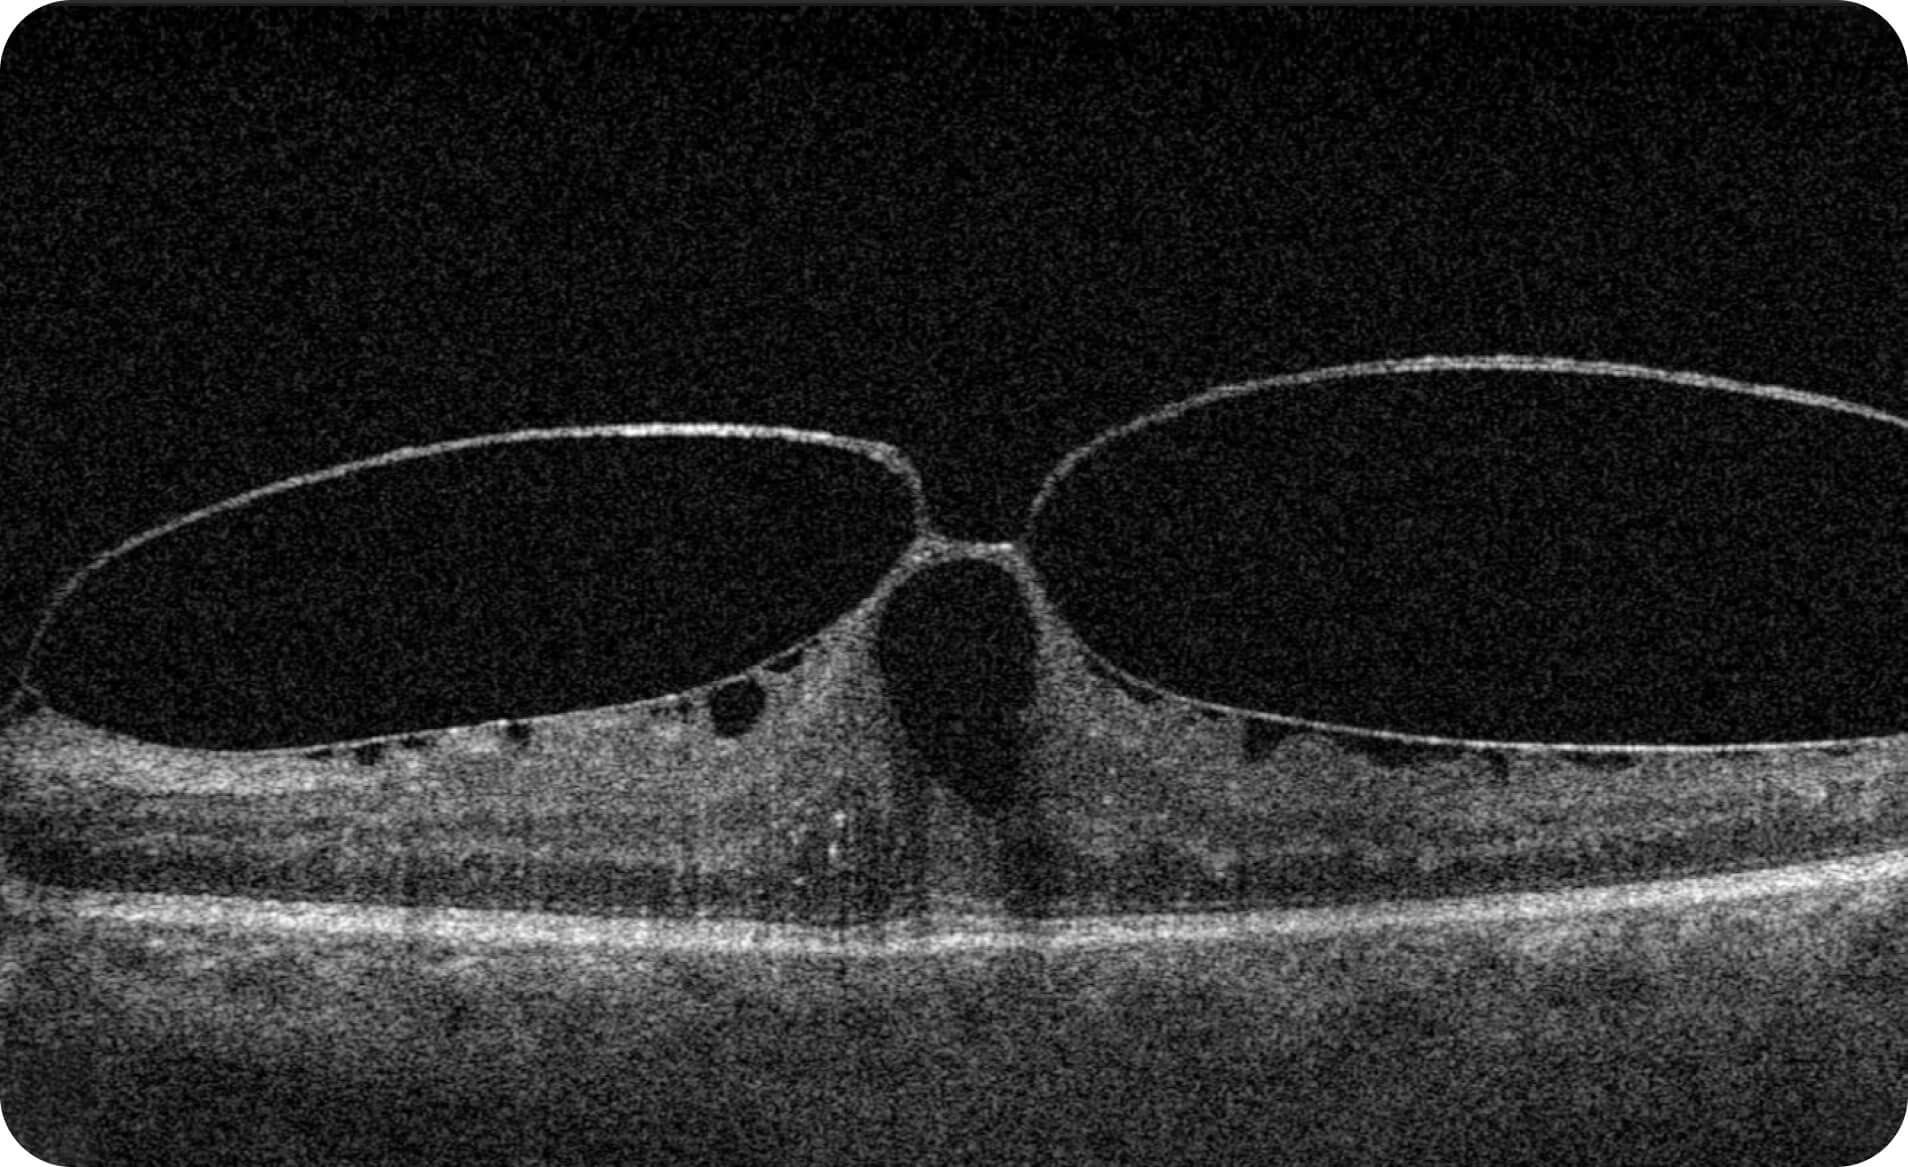

Characterization and visualization of OCT features commonly studied in Geographic Atrophy (GA), including hypertransmission, RPE atrophy, neurosensory retinal atrophy, and EZ changes.

Altris is a web platform developed by professionals with expertise in retinal imaging. We’ve collected a large number of OCT scans, and our team has manually annotated thousands of them to develop the Altris system, an artificial intelligence geographic atrophy research USA platform, which can:

- 40+retinal biomarkers studied in research across 30+ retinal conditions. For Research Use Only. Not for diagnostic procedures.

- Quantitative exploration of 40+ biomarkers for Research Use Only. Not for diagnostic procedures.